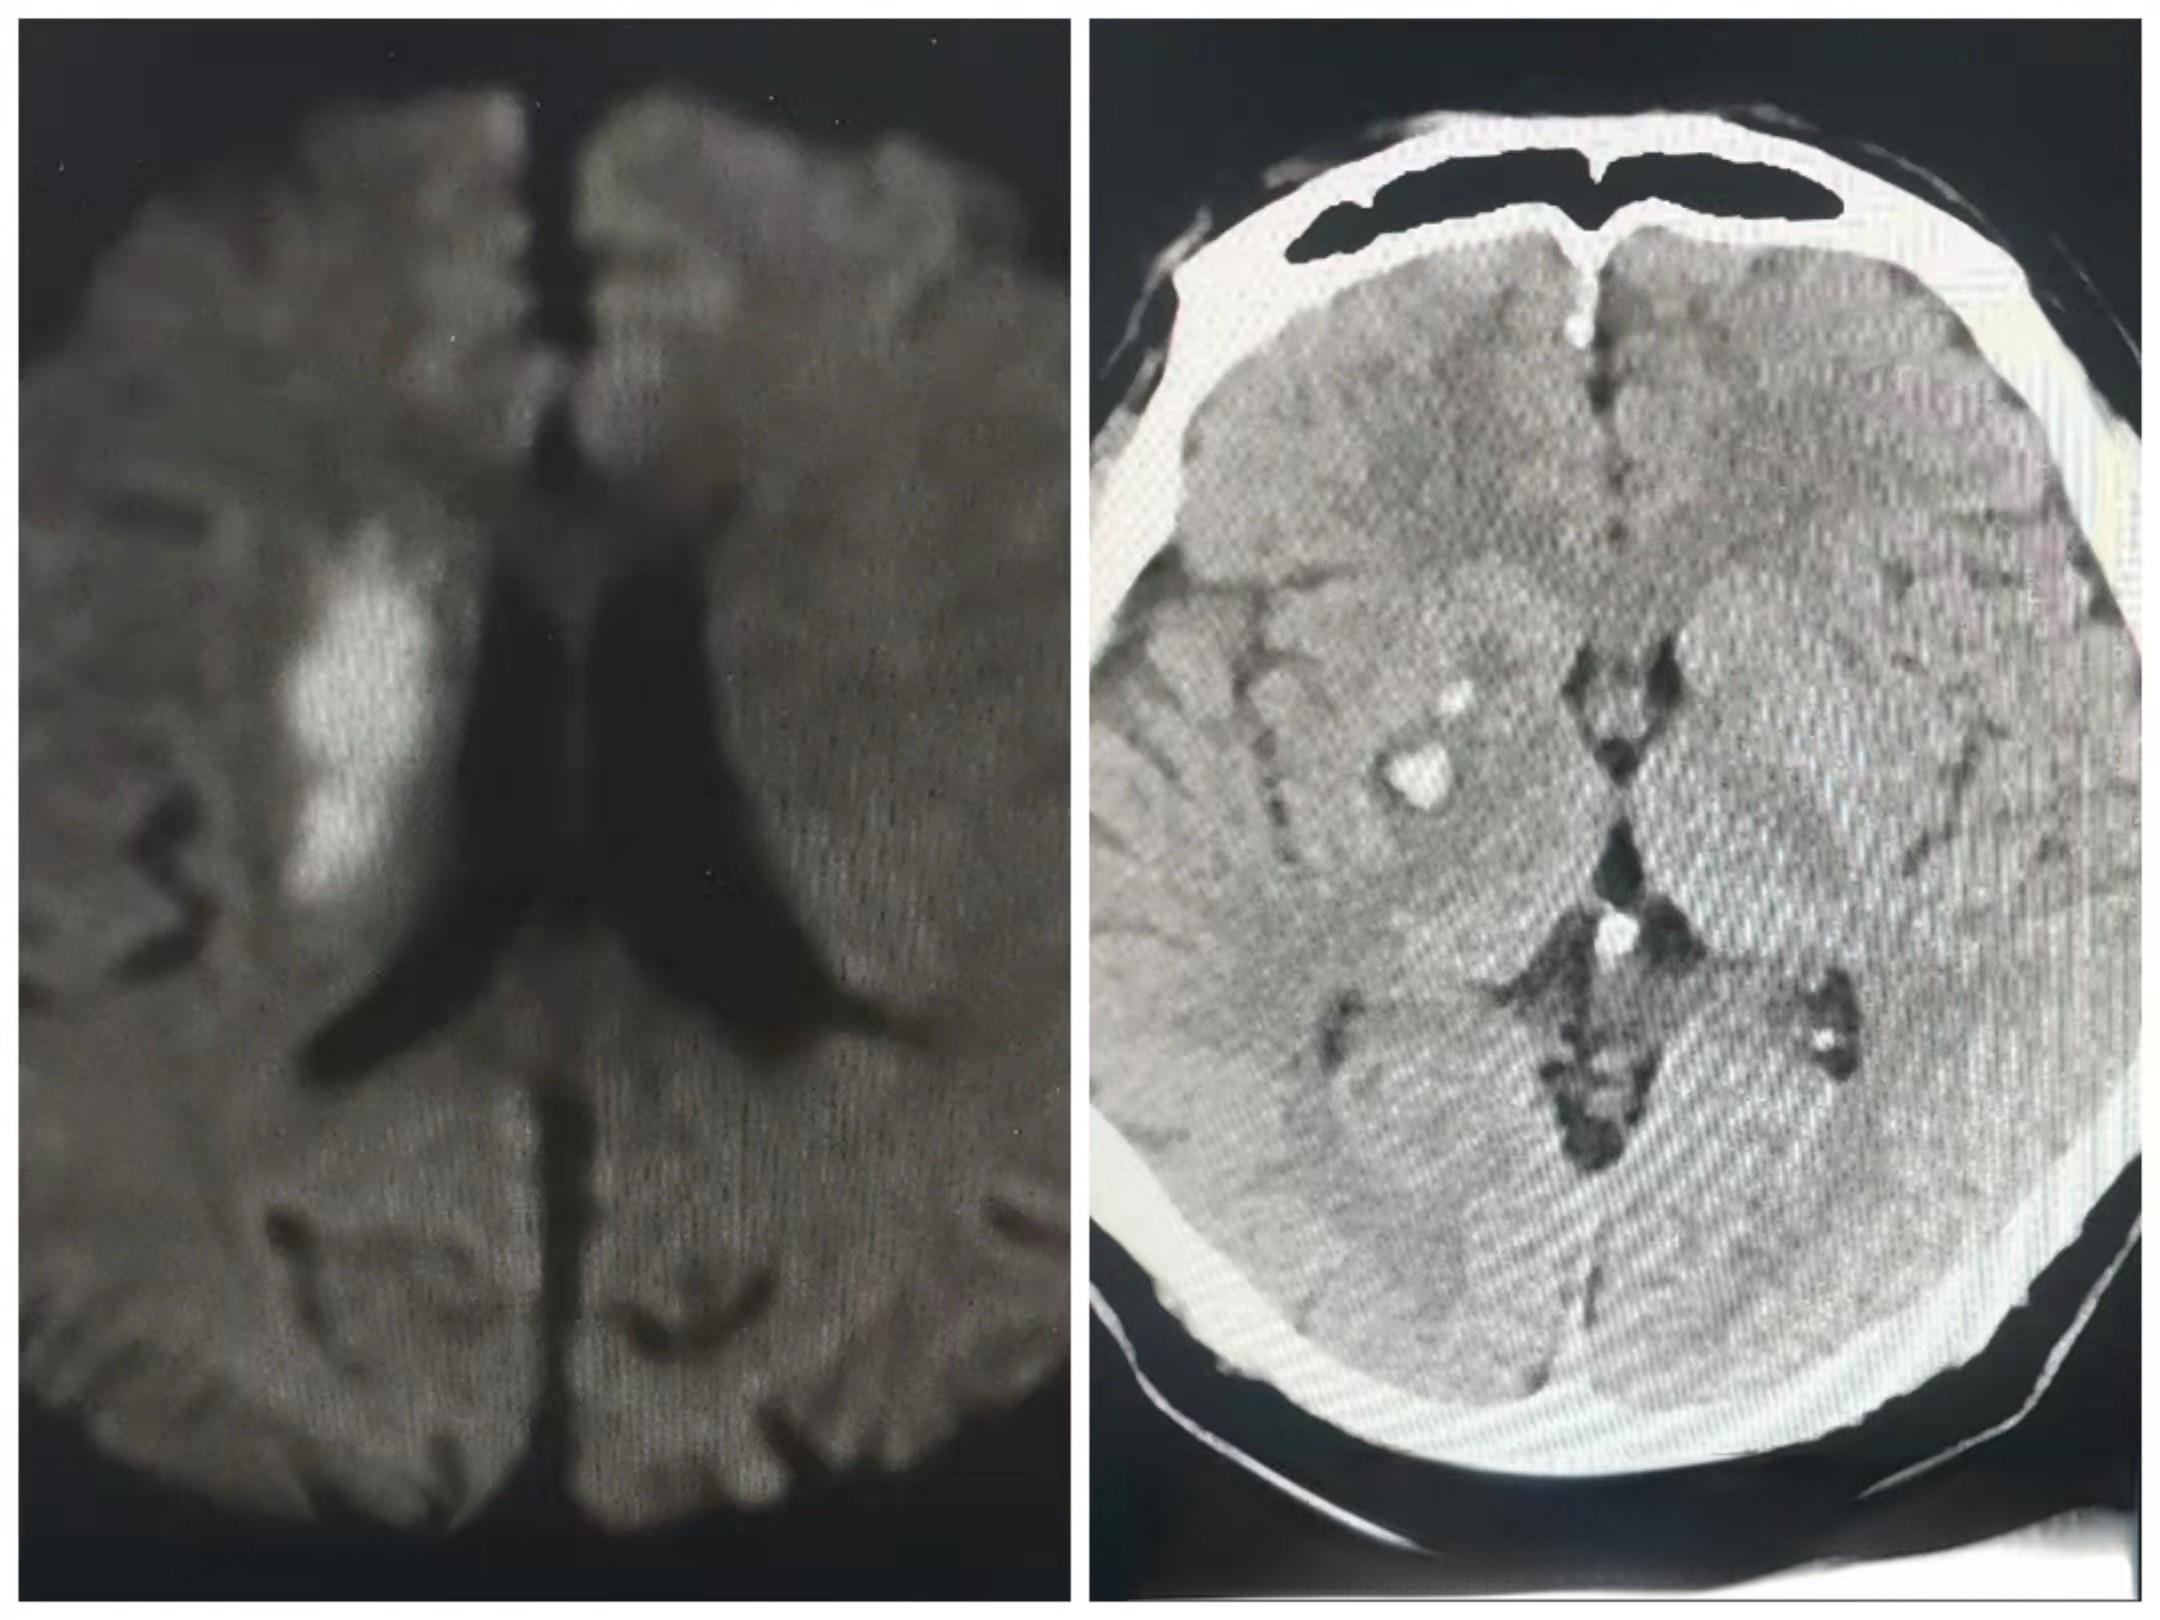

近日,北京市丰台中西医结合医院脑病中心成功为一名急性缺血性脑血管病患者实施溶栓治疗,挽救了患者的生命。这名患者因“右侧肢体无力并伴有言语不利达1.5小时”被紧急送院。医院立即启动脑卒中绿色通道,在1小时内完成了静脉溶栓治疗。治疗后,患者言语不利及口角歪斜状况显著改善,右侧肢体肌力恢复正常。